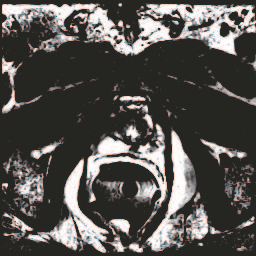

In this paper, we focus on three problems in deep learning based medical image segmentation. Firstly, U-net, as a popular model for medical image segmentation, is difficult to train when convolutional layers increase even though a deeper network usually has a better generalization ability because of more learnable parameters. Secondly, the exponential ReLU (ELU), as an alternative of ReLU, is not much different from ReLU when the network of interest gets deep. Thirdly, the Dice loss, as one of the pervasive loss functions for medical image segmentation, is not effective when the prediction is close to ground truth and will cause oscillation during training. To address the aforementioned three problems, we propose and validate a deeper network that can fit medical image datasets that are usually small in the sample size. Meanwhile, we propose a new loss function to accelerate the learning process and a combination of different activation functions to improve the network performance. Our experimental results suggest that our network is comparable or superior to state-of-the-art methods.